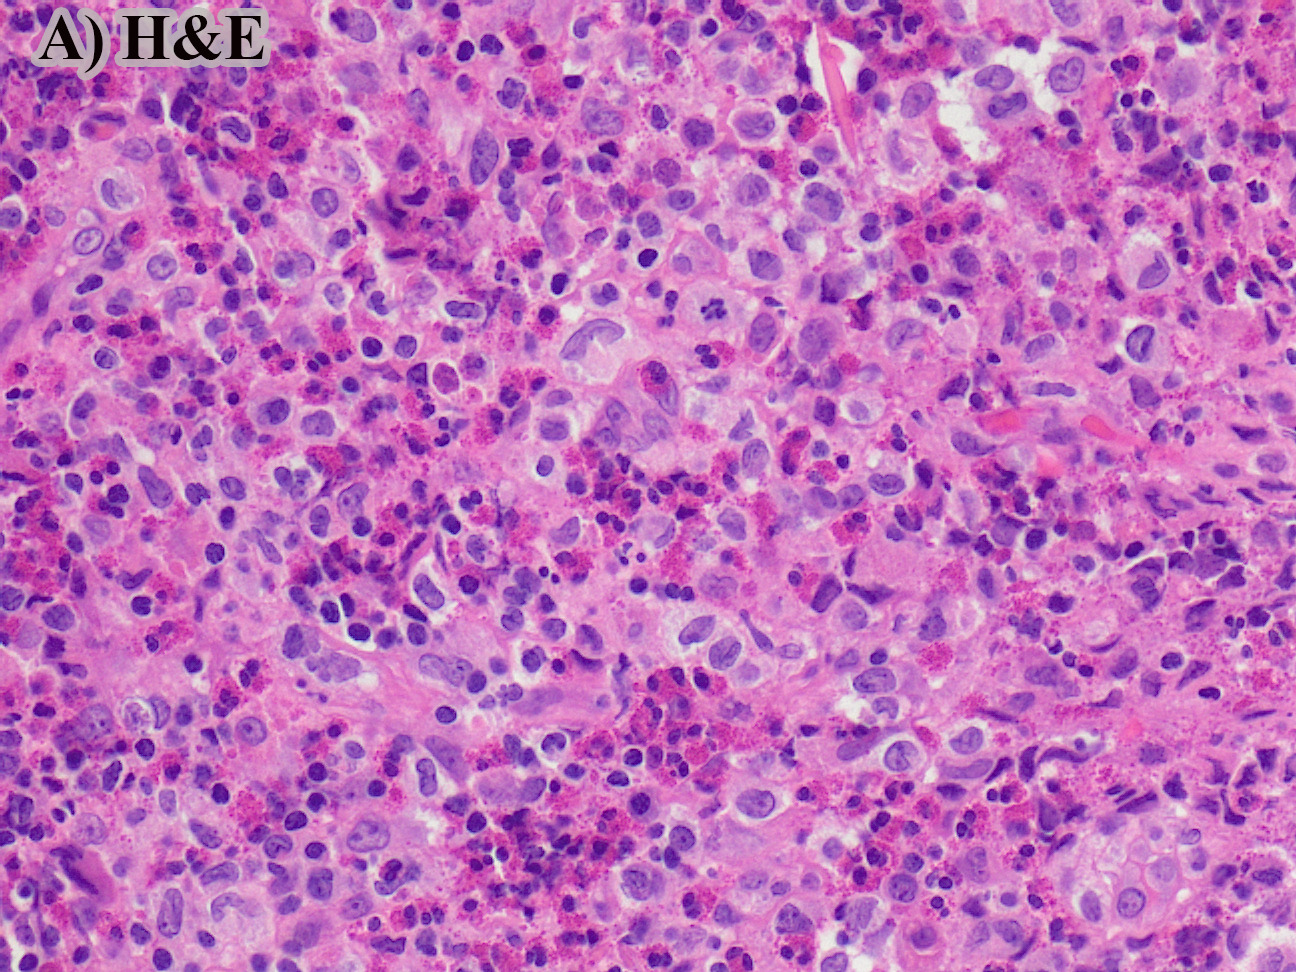

40 year old male found unresponsive. No medical or social history. The scene was unremarkable. External examination revealed scars on the forearms and legs. Autopsy revealed 450 g heart, edematous lungs, and firm liver.